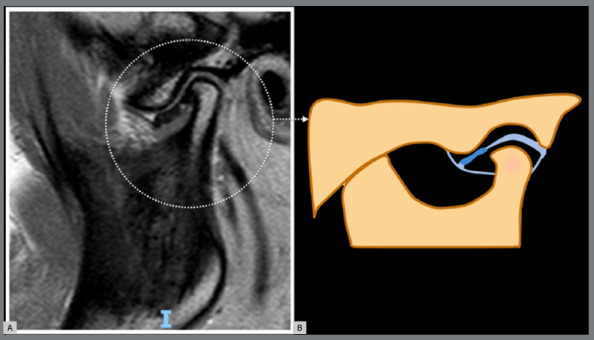

导言:骨关节炎(OA)是一种渐进性退行性疾病,以软骨逐渐退化、软骨下骨重塑、滑膜炎和慢性疼痛为特征。这种疾病会影响各种大小关节,包括颞下颌关节(TMJ)。然而,由于临床和影像学上的异质性,治疗 OA,尤其是阻止或减少疾病进展具有挑战性。越来越多的学者认为,这种异质性涉及不同的表型或亚群,可通过疾病的病理生理学和结构表现的差异来辨别。即使在颞下颌关节内,这些表型也可能显示出不同的临床特征、实验室参数、生化标志物和成像标准。最近的研究提出将核磁共振成像作为颞下颌关节 OA 的参考标准,强调其与组织病理学变化高度一致。基于核磁共振成像的表型为了解疾病进展和治疗反应提供了一条很有前景的途径,有可能为预后和治疗计划提供有价值的见解:本文介绍了ROAMES-TMJ(颞下颌关节骨性关节炎MRI快速合格评分),用于评估颞下颌关节OA临床试验的结构合格性。

Introduction: Osteoarthritis (OA) is a progressive degenerative disease characterized by the gradual degradation of cartilage, remodeling of subchondral bone, synovitis, and chronic pain. This condition impacts various large and small joints, including the temporomandibular joint (TMJ). However, addressing OA, particularly in impeding or reducing disease progression, is challenging due to its clinical and imaging heterogeneity. Authors are increasingly suggesting that this heterogeneity involves different phenotypes or subpopulations, discernible by variations in the disease's pathophysiology and structural manifestations. Even within the TMJ, these phenotypes may display distinct clinical features, laboratory parameters, biochemical markers, and imaging criteria. Recent research has proposed MRI as a reference standard for TMJ OA, highlighting its substantial agreement with histopathological changes. MRI-based phenotypes offer a promising avenue for understanding disease progression and treatment response, potentially providing valuable insights for prognosis and treatment planning.

Objective: This article introduces the ROAMES-TMJ (Rapid OsteoArthritis MRI Eligibility Score for TMJ) to assess the structural eligibility of individuals for inclusion in TMJ OA clinical trials.